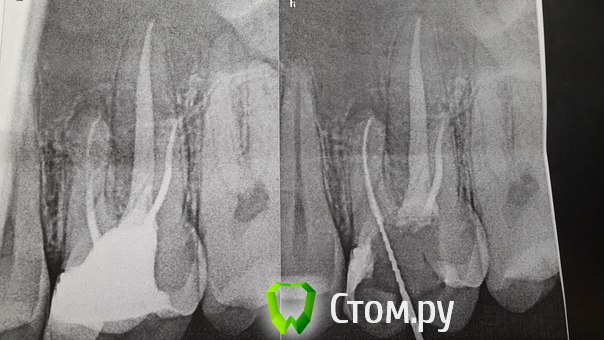

M@estro Опубликовано 2 декабря, 2013 Автор Поделиться Опубликовано 2 декабря, 2013 (изменено) Спасибо всем за оценку. Сегодняшний. зуб 4.4. Был хронический пульпит. Первое посещение - первичная обработка, кальций. Второе - обработка канала, снимок немного в другой проекции - вижу ,что корень раздваивается... Начинаю искать... нашёл язычный, ответвляется не сказать что очень глубоко, но под навесом был, в полость входил сбоку, сходу не видно. Опять кальций. Третье посещение - обработка M - two до iso 30 , обтурация. Увеличения нет. Мог ведь и пропустить,но повезло. http://s017.radikal.ru/i426/1312/cb/2a921769fd9f.jpg Изменено 2 декабря, 2013 пользователем M@estro 12 Ссылка на комментарий

M@estro Опубликовано 5 декабря, 2013 Автор Поделиться Опубликовано 5 декабря, 2013 (изменено) Покажите плиз первичный снимок до эндо Участок ортопантомограммы,прицельный перед эндо не делал : http://i016.radikal.ru/1312/81/3224fff58f4b.jpg Снимок с рд (как мне казалось), на котором увидел, что пора бы поискать второй : http://s020.radikal.ru/i721/1312/ce/6967f559f3b2.jpg Если внимательно посмотреть, то и на орто видно место фуркации. Изменено 5 декабря, 2013 пользователем M@estro Ссылка на комментарий

Л Ю С Я Опубликовано 6 декабря, 2013 Поделиться Опубликовано 6 декабря, 2013 На орто видно что 2. Ох уж эти нижние премоляры, вечно сюрпрайзы. Выводы: надо внимательно изучать снимки до , во время и после. Ссылка на комментарий